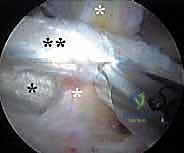

3. النوع داخل المفصلي (Intra-articular Snapping Hip)

وهو الأقل شيوعًا ولكنه الأكثر تعقيدًا. على عكس النوعين السابقين اللذين يحدثان خارج المفصل، ينتج هذا النوع عن مشاكل ميكانيكية داخل مفصل الورك نفسه. لا يتعلق الأمر هنا باحتكاك الأوتار، بل بوجود عوائق مادية داخل المفصل تعيق الحركة السلسة.

* تمزقات الشفة الحرقفية (Acetabular Labral Tears).

* وجود أجسام حرة (Loose Bodies) داخل المفصل، مثل شظايا صغيرة من العظم أو الغضروف المكسور.

* عيوب وتلف في الغضروف المفصلي الناعم الذي يغطي العظام.

* الاصطدام الفخذي الحُقي (Femoroacetabular Impingement - FAI).

يتطلب هذا النوع تشخيصًا دقيقًا للغاية لاستبعاد الأسباب الأخرى، وغالبًا ما يكون التدخل بالمنظار هو الحل الأمثل له.